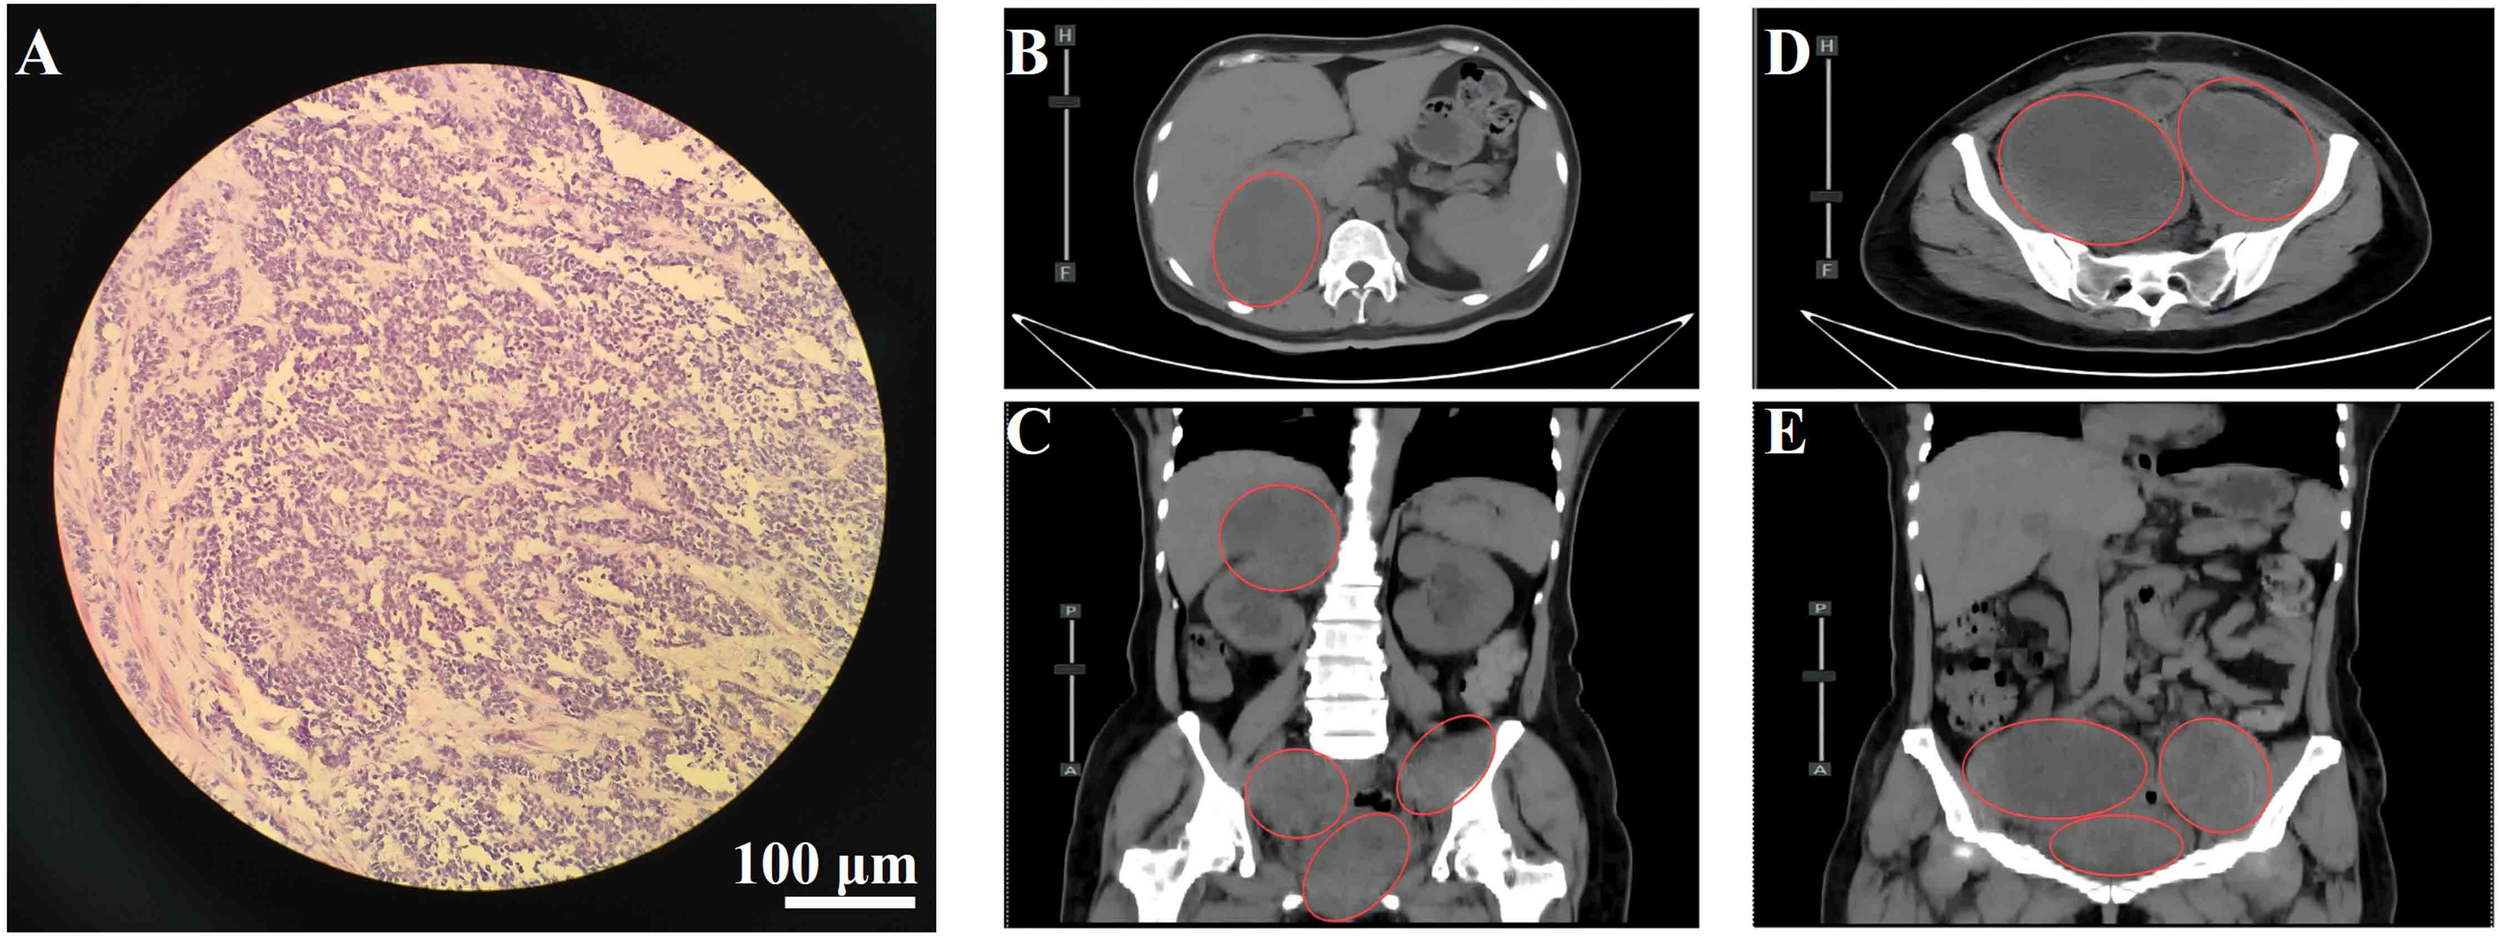

Figure 1

(A) Hematoxylin and eosin (H&E) staining of cervical tissue showing malignant melanoma. Scale bar = 100 μm; magnification, 200×. (B) Axial view of lesion in the hepatorenal space. (C) Coronal view of the hepatorenal space lesion. (D) Axial view of pelvic lesion. (E) Coronal view of the pelvic lesion. Red circles indicate metastatic lesions.

The patient is a 54-year-old female who presented with a four-month history of a cervical mass, discovered on routine gynecological examination on September 14, 2023. Physical examination revealed a 4 × 3 × 2 cm red, papillary, lobulated mass located on the anterior lip of the cervix. The lesion had a smooth surface and exhibited slight hemorrhagic changes. On September 15, 2023, a hysteroscopic examination was performed, and pathology showed proliferative endometrium in the uterine cavity (Figure 1A). The immunohistochemical results show AE1/AE3 (−), CD20 (−), CD3 (−), CD56 (partially +), CD10 (partially +), ER (−), CEA (−), CgA (−), Desmin (−), P16 (−), Ki-67 (index 80%), PR (−), p53 (wild-type), S-100 (+), Syn (−), SMA (−), TTF-1 (−), with scattered positivity for Melan-A and HMB45, and diffuse positivity for SOX10. Based on the histopathological and immunohistochemical findings, a diagnosis of primary malignant melanoma of the cervical mucosa was rendered.

On January 17, 2024, the patient underwent a radical hysterectomy, bilateral adnexectomy, and pelvic lymph node dissection under general anesthesia. Pathology confirmed cervical malignant melanoma (pT4aN0M0, stage IIB). The tumor was located in the cervical canal, measuring 3 × 3 cm, and invaded nearly the full thickness of the cervix. There were no signs of vaginal wall involvement, and the lymph nodes (left 8, right 6) were negative for metastasis. Immunohistochemistry was positive for Vimentin, S-100, SOX10, HMB45, Melan-A, and Ki-67 (80%+), with negative markers for CD45 and CK(P). No adjuvant therapy was administered postoperatively due to the patient’s refusal. The patient was readmitted on August 12, 2024, due to worsening bilateral leg pain for 3 weeks, which had intensified in the past week. On August 14, 2024, an abdominal CT revealed multiple metastatic lesions, including a low-density mass at the liver’s right lobe boundary measuring 3.3 × 3.5 cm, masses in the retroperitoneal space, right kidney, and pelvis with significant tumor invasion near the bladder and rectum, and bone destruction in the T10 vertebra, suspected to be metastatic (Figures 1B–E). These findings were consistent with disease recurrence, now classified as cT4aN0M1c, stage IV, with metastases to the bladder, rectum, liver, lungs, bones, abdomen, and pelvis.